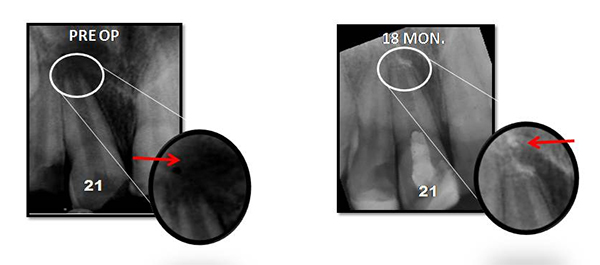

PRF Mediated REP in 21 with 18 Months Follow Up

Complete Bony Healing, Apex Closed, Lateral Wall Thickening- 15.5%

PRP Mediated REP in 21 with 18 months follow up

Bone healing, Apical PDL formed, Apex Closed, Calcific Bridge formed in 21.

Vitality Positive